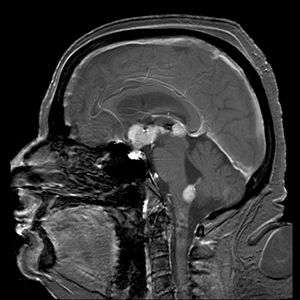

| Brain magnetic resonance imaging showing primary central nervous system B-cell non-Hodgkin lymphoma of the sella turcica and hypothalamus, continuing to the tectum (intensely white areas in the middle). | |

MRI or contrast enhanced CT classically shows multiple ring-enhancing lesions in the deep white matter. The major differential diagnosis (based on imaging) is cerebral toxoplasmosis, which is also prevalent in AIDS patients and also presents with a ring-enhanced lesion, although toxoplasmosis generally presents with more lesions and the contrast enhancement is typically more pronounced. Imaging techniques cannot distinguish the two conditions with certainty, and cannot exclude other diagnoses. Thus, patients undergo a brain biopsy.